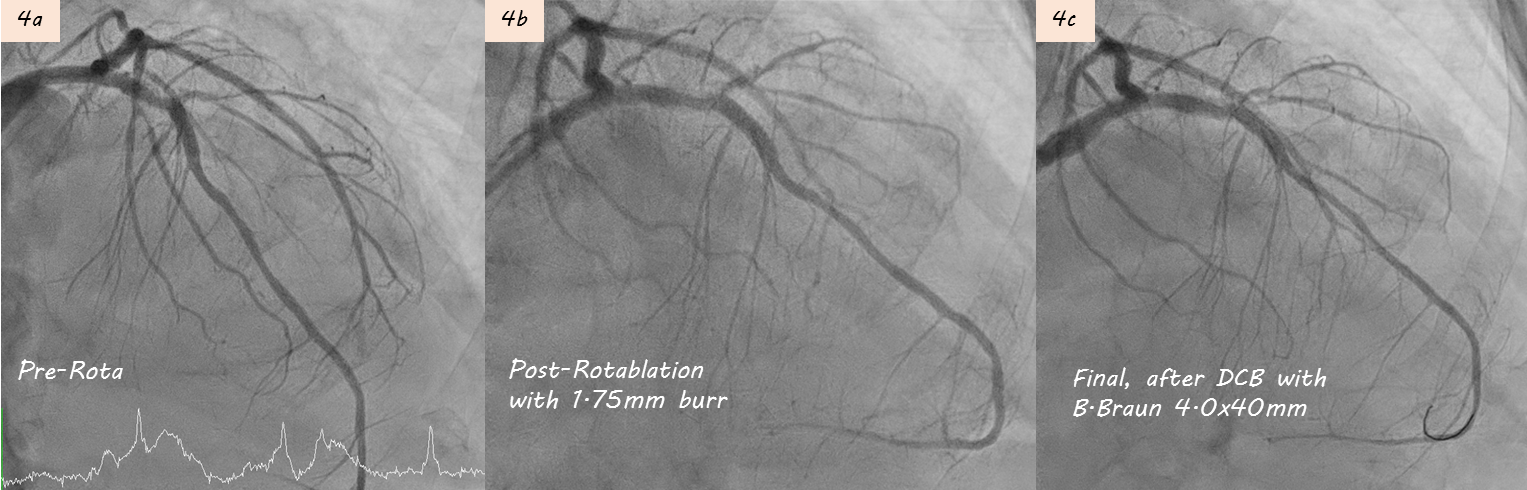

During 1st PCI, IVUS showed severe calcification in LAD seg6 (Fig. 2a). Rotablation with a 2.0 mm burr was performed (Fig. 2b), and a 3.5¡¿28mm Multi-Link BMS was implanted but remained underexpanded (Fig. 2c).STEMI developed one week later prompted repeat CAG showing subacute thrombosis within LAD stent (Fig. 3a). Thrombus aspiration was performed. POBA with a 3.5¡¿15mm Raiden balloon (up to 24 atm) failed to fully expand the stent (Fig 3b). Subsequently, a 3.5¡¿30mm MagicTouch DCB was used.During 3rd PCI,rotational atherectomy was performed with 1.75mm and then 2.0mm burrs; however, 2.0 mm burr entrapment occurred during lesion crossing, and angiography showed limited debulking effect (Fig 4a-b). High-pressure balloon with APT NC 3.5x12mm were attempted but rupture(30 atm). We then POBA with Raiden 3.5¡¿15mm (30 atm), Raiden 4.0¡¿15 mm (32 atm), and NC Euphora 4.5¡¿15mm (20 atm). Finally, 4.0x40mm B. Braun DCB angioplasty was performed (Fig 4c).4th PCI was performed 1 month later for intravascular lithotripsy (IVL) and new stent implantation. Second time rotablation with a 1.75 mm burr was performed (Fig. 5a-b). IVL with a 4.0¡¿12mm balloon (100 pulses) achieved adequate expansion (Fig. 5c–d). Adequate POBA were followed by final stenting using a 4.0¡¿23mm Firehawk DES (Fig. 5e). Proximal optimization technique and kissing balloon technique were performed (Fig. 5f). Serial IVUS showed better debulking after 2nd Rotablation and IVL, and adequate new stent expansion (Fig 6a-6f).